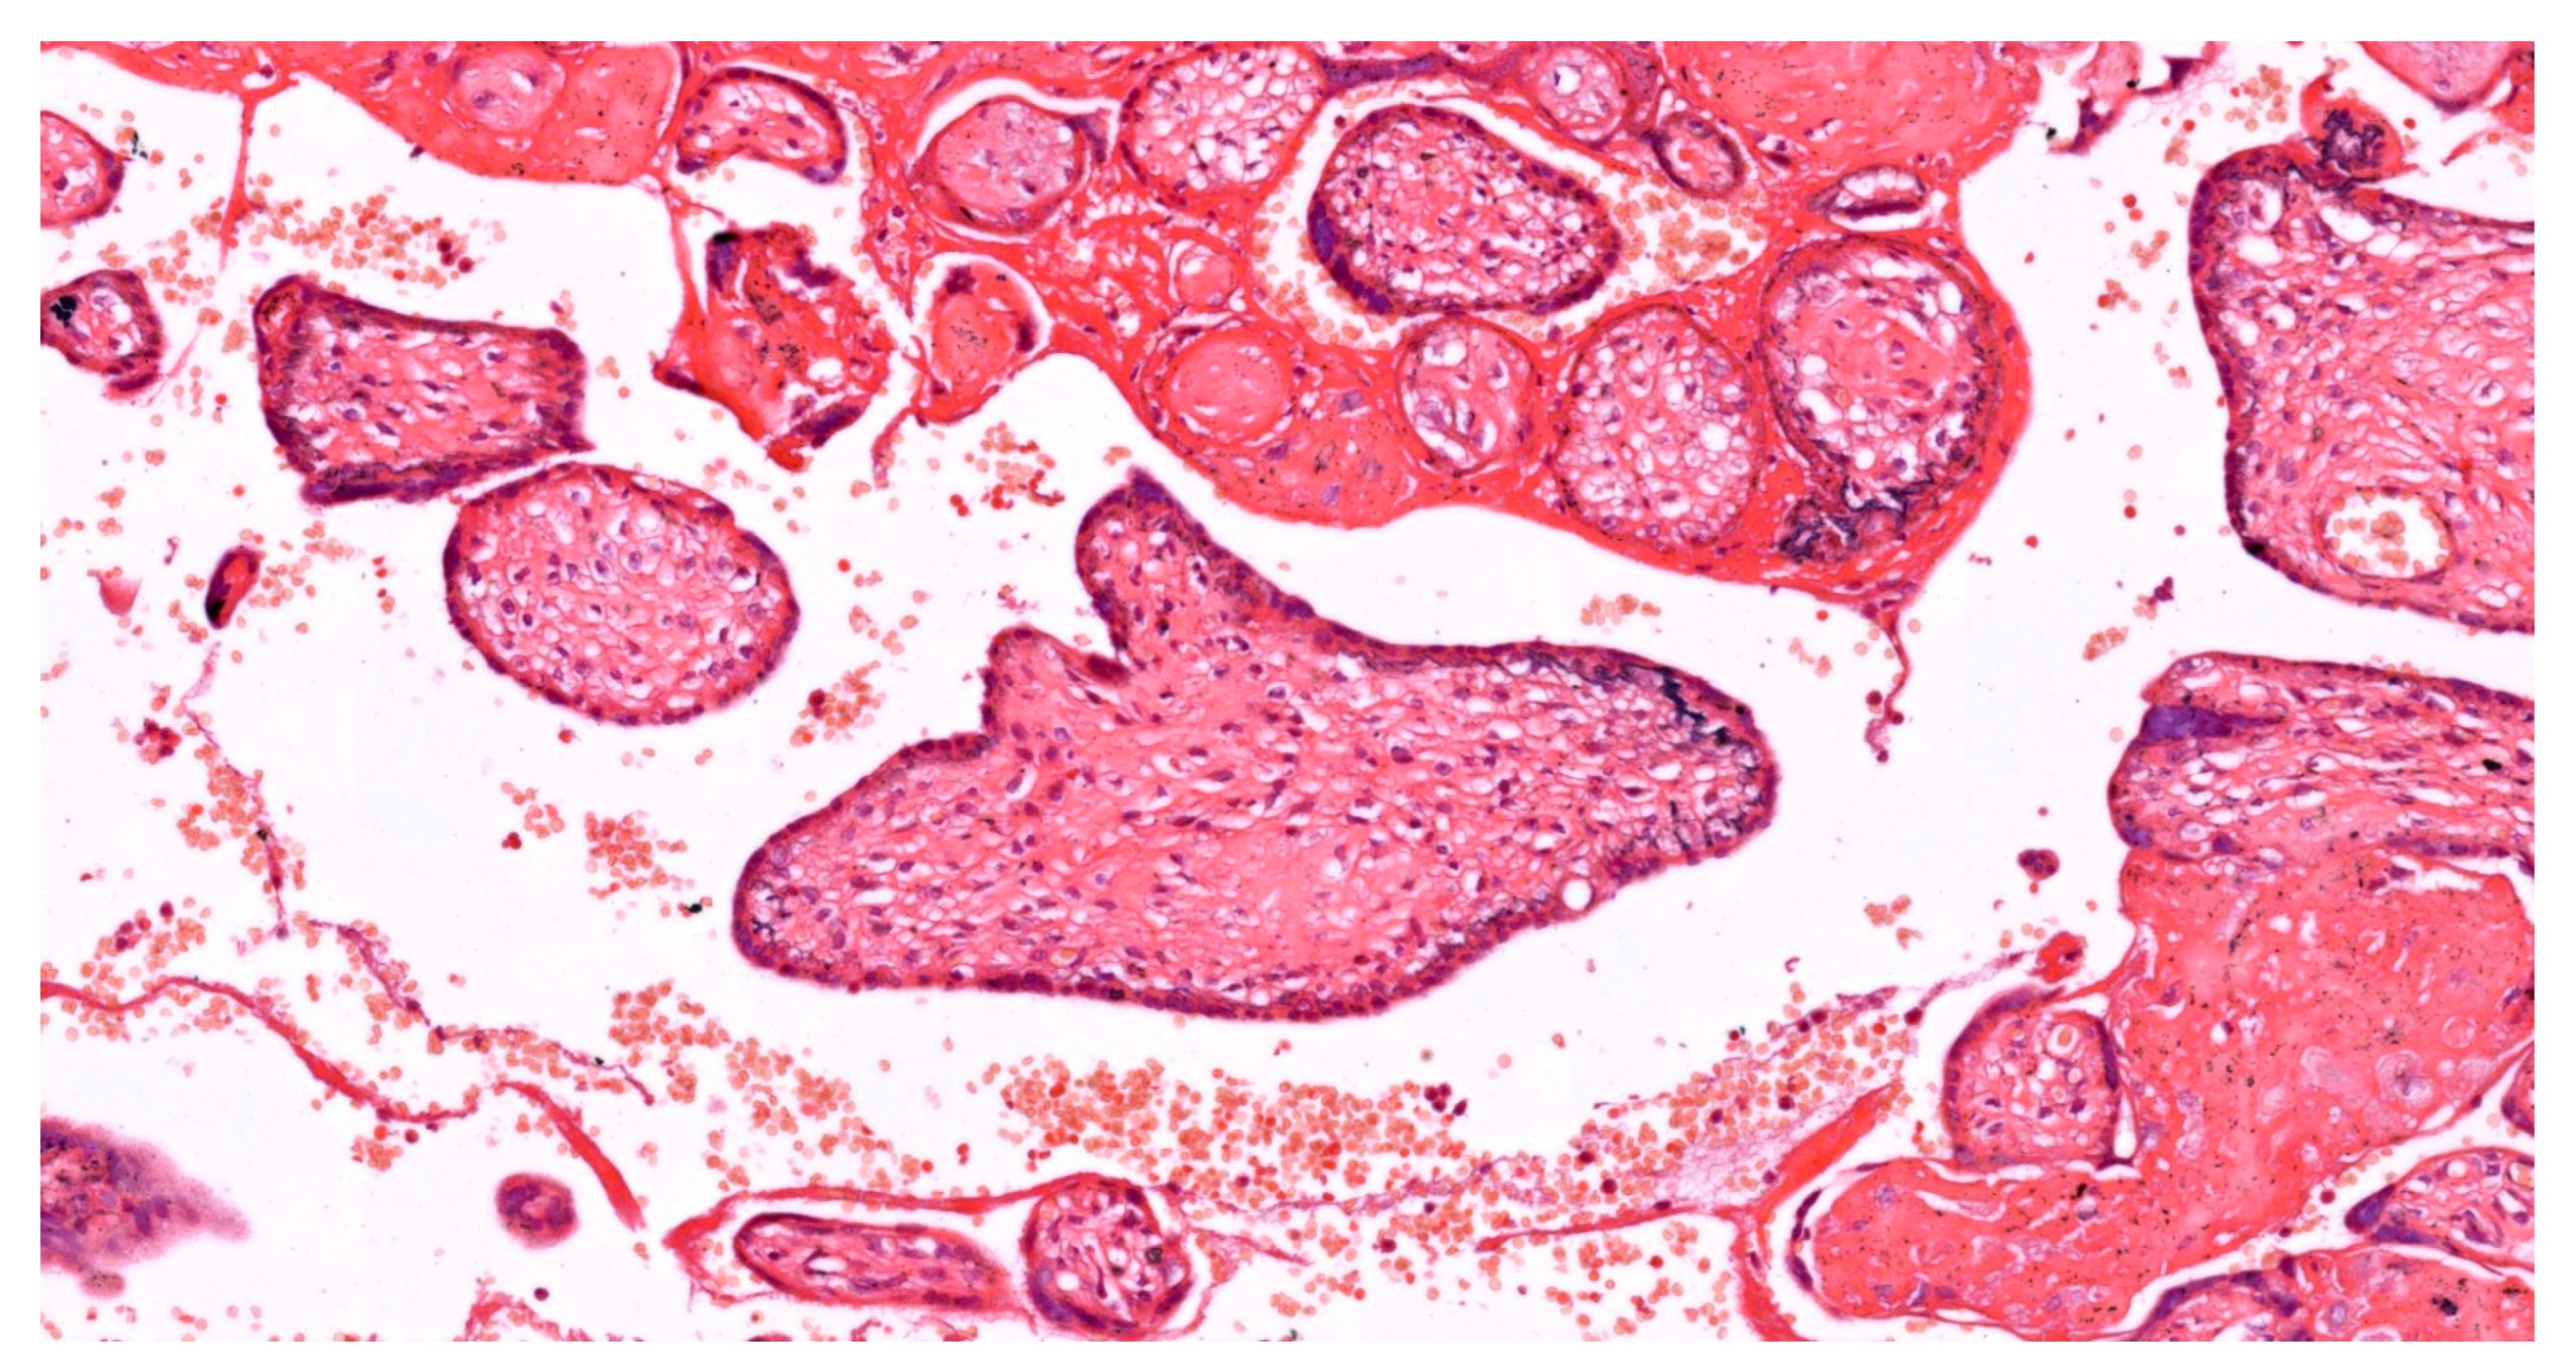

Structural adaptations are another response to OS. While excessive syncytial knots are pathological, a moderate increase may represent an adaptive response to shed damaged syncytiotrophoblasts. Chorangiosis, or the increased vascularization of terminal villi, can occur in response to hypoxia, potentially improving oxygen delivery (see Figure 3). The thickening of the vasculosyncytial membrane may serve as a protective barrier against oxidative insults [118].